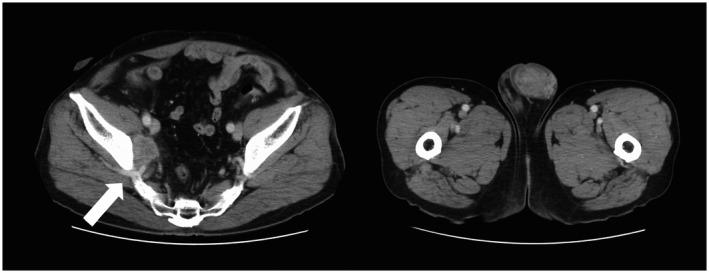

A 68-year-old man presented with gross hematuria and urinary frequency. Cystoscopy demonstrated an 8-cm-sized tumor in the bladder; transurethral resection and magnetic resonance imaging confirmed invasive urothelial carcinoma. Cystoprostatourethrectomy was performed, and the pathological diagnosis was high-grade muscle-invasive urothelial carcinoma. Three years later, the patient noticed a left scrotal mass. Left high orchiectomy was performed, and histopathologic examination of the surgical specimen revealed urothelial carcinoma, confirming testicular metastasis derived from bladder cancer. The patient received chemotherapy with gemcitabine and cisplatin and has survived for 7 years since the initial diagnosis without progression.

一名68岁男性出现肉眼血尿和尿频症状。膀胱镜检查发现膀胱内有一个8厘米大小的肿瘤;经尿道切除术和磁共振成像证实为浸润性尿路上皮癌。进行了膀胱前列腺尿道切除术,病理诊断为高级别肌层浸润性尿路上皮癌。三年后,患者发现左侧阴囊肿块。进行了左侧高位睾丸切除术,手术标本的组织病理学检查显示为尿路上皮癌,证实为源自膀胱癌的睾丸转移。患者接受了吉西他滨和顺铂化疗,自初次诊断以来已存活7年且无病情进展。